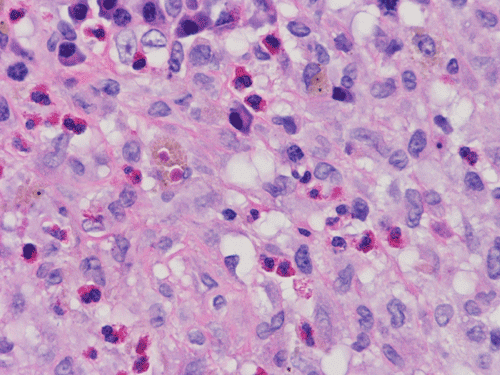

At scanning magnification (Panel A), the lung parenchyma is replaced by some coalescing fibrous nodules. The degree of involvement is variable at different fragments (Panel B and C). In the less affected areas, there are some fibrotic thickening of the septa (Panel C). In some areas, the changes are minimal and the pleural appear to be uninvolved (Panel D and E). In low to medium magnifications, these nodules of fibrosis contains a large number of hemosiderin laden macrophages (Panel F and G) admixed with fibrous tissue. The diagnostic tissue, however, is present in areas with increased cellularity. In these areas, there is a background of cells with a moderate amount of cytoplasm and bland nuclei. Some of these nuclei have kidney shape (arrow in Panel H). In some areas, many of the nuclei have a deep nuclear groove that resemble a coffee bean (arrow in Panel I). In the third type of areas, the nuclear grooving is not distinct (Panel J). Prominent eosinophilic infiltrations are almost always present. Immunohistochemistry on CD1a revealed many positive cells (Panel L). Also present in the specimen are multiple small blood vessels with thickened intima (Panel K). A Movat pentachrome stain demonstrates an internal elastic layer in these vessels and confirms that these are arteries (Panel M and N).

Pathologically, PLCH can be broadly divided into an early or cellular stage and a late or fibrotic stage. Demonstration of LCs is of critical importance for a correct diagnosis. The morphology of LCs is similar to LCH in other organs. LCs are characterized by a deep nuclear groove which lead to “coffee bean-shaped” or “kidney-shaped” nuclei. In most cases, the level of atypia and pleomorphism is low. A moderate amount of amphophilic to weakly eosinophilic cytoplasm is present. The cytoplasmic membrane is indistinct. Eosinophils and chronic inflammatory cells, varying from scant to abundant, are present. Except for a scant frankly pleomorphic cases, the level of pleomorphism and atypia is minimal to low. Eosinophilic abscesses with central necrosis may be present. Immunohistochemically, LCs are similar to their normal counter parts and are positive for CD1a and S100. At the ultrastructural level, Birbeck granules can be demonstrated. For most cases, the diagnosis can be established by histopathologic criteria but these additional features help to confirm the diagnosis.

In the early stage of PLCH, there are interstitial infiltrates composed of LCs, lymphocytes, macrophages, eosinophils, plasma cells and fibroblasts 4. The infiltrates enlarge to form nodules centered on the small airways. Brown pigmented macrophages (smokers macrophages) are present in and around the nodules. Eosinophils tend to localize at the innermost layer of the nodules, where LCs can be most easily found in the thickened interstitium. Associated patchy interstitial and airspace organization or respiratory bronchiolitis may be present. Other smoking related changes are also common. Cavitation often occurs within the nodules which represents either an airway remenant or de novo cavitation as the inflammatory infiltrate enlarges. There is centripetal replacement of the nodules by fibroblasts which produce the classic stellate lesions of PLCH. As the disease progresses, the number of nodules, cavitary granulomas and fibrotic scars increase in number.